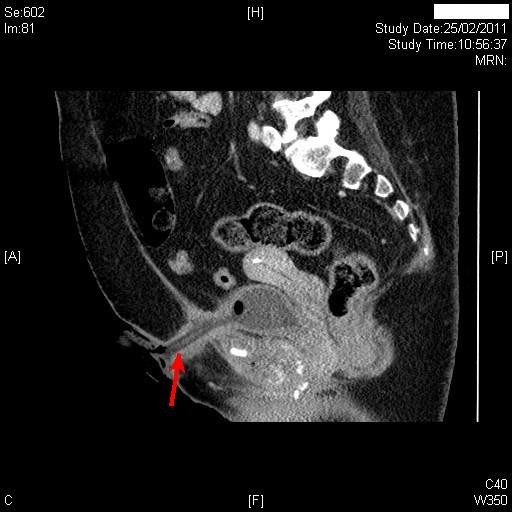

Suprapubic Catheterization for Urinary Drainage